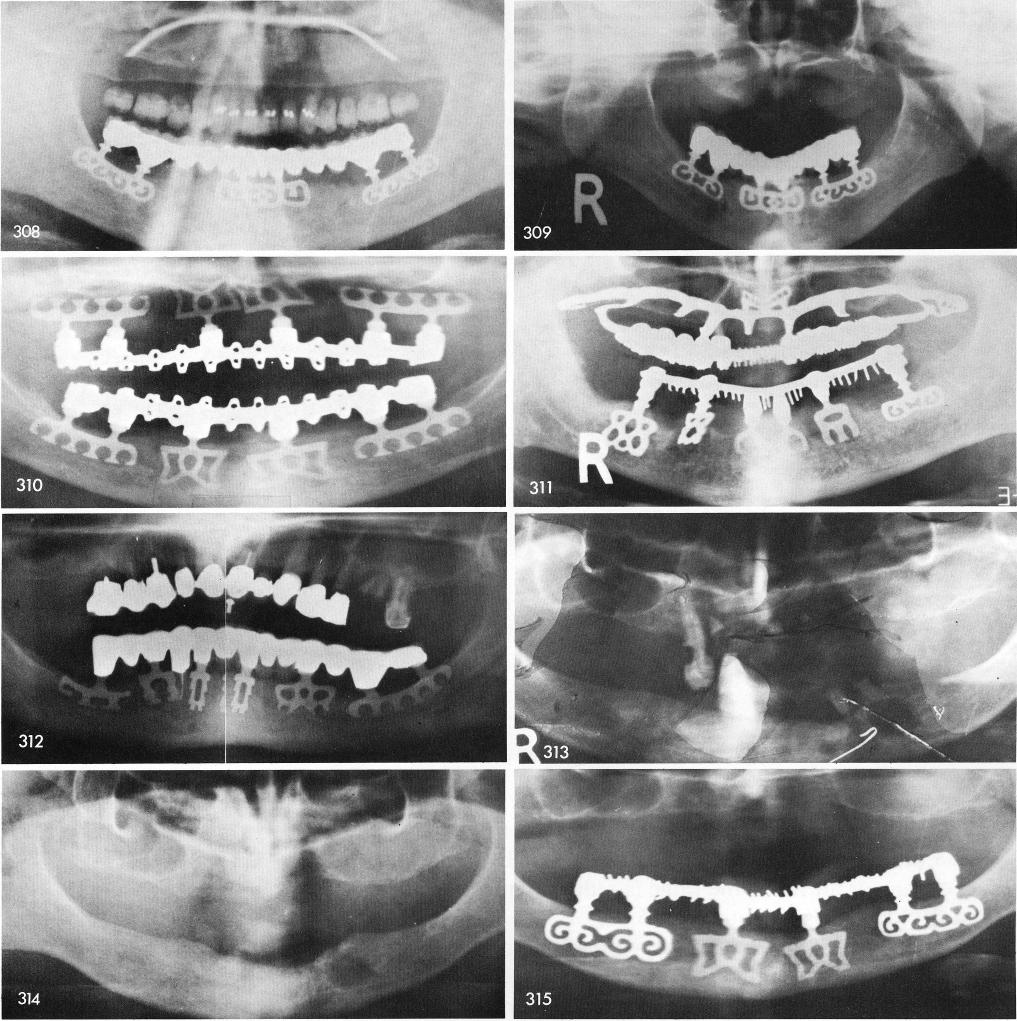

Fig. 313 shows a case with an odontoma of a large residual cyst in the lower left bicuspid region. Also, a mass of tartar existed around and below the right cuspid.

Fig. 314 shows post-operative x-ray revealing the cyst still persisting.

Fig. 315 is an x-ray after two years of lower blades. The cyst had filled in with bone.

1 X-rays of totally edentulous mandibular blade implant cases